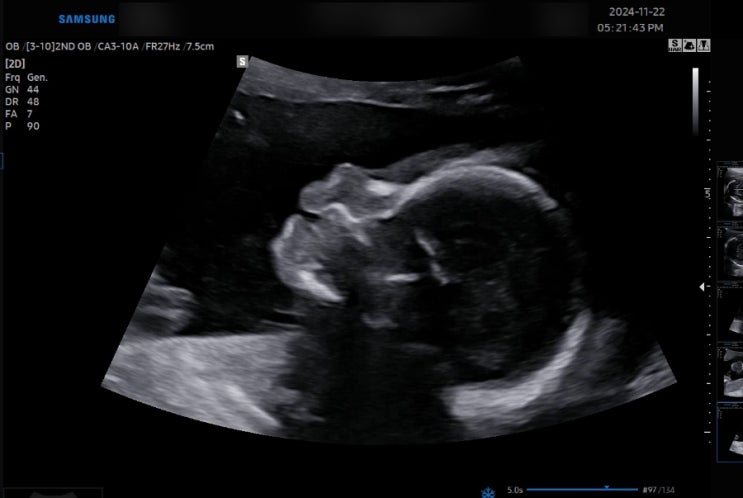

임신 21주 차 정밀 초음파에는 어떤 걸 확인하는 걸까? / 큐트루

안녕하세요 큐트루예요. 임신 21주 차 정밀 초음파에는 어떤 걸 확인하는 걸까? 포스팅합니다. 정밀 초음파...